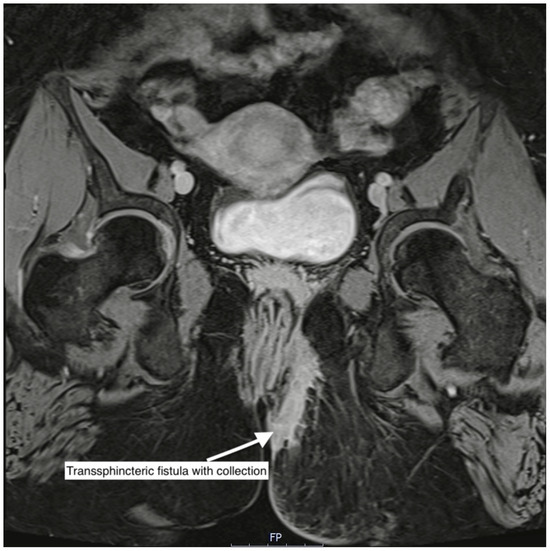

| Transsphincteric | 153 | 61.2 | |